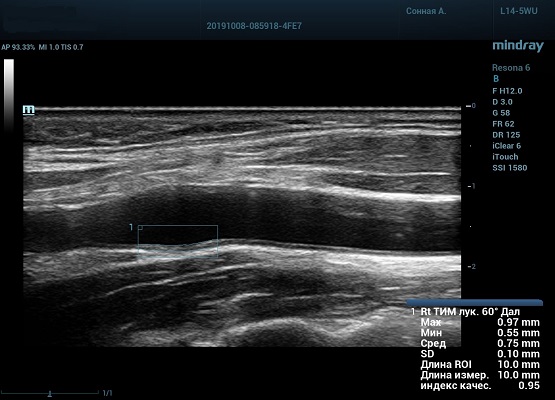

На сегодняшний день измерение IMT происходит автоматическим путем при использовании функции AUTO-IMT. Необходимо указать прибору зону интереса, стандартной длиной (1 см), в которой происходит отслеживание кромок и выдача максимального, среднего и минимального значения. УЗИ аппараты компании Mindray среднего, экспертного и премиального класса снабжены данной функцией и позволяют контролировать не только полученные значения, но и оценить точность измерения кромки в конкретной зоне по индексу качества. Используя индекс качества, легко решить, можно ли использовать полученное значение.